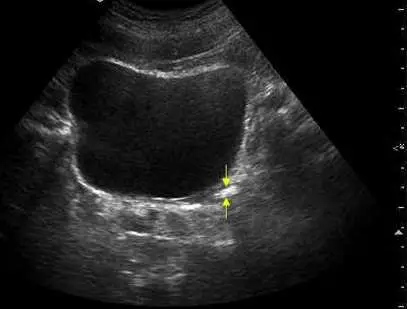

下圖 45 歲左腰痛男性病患膀胱之超音波影像中箭號所指為何?

本張超音波影像標示為腹部(Abdomen)掃描,使用 4C1-S 探頭(4.0 MHz),可見:

- 影像中可見一大型無回音結構(膀胱)

- 白色箭號指向膀胱後外側壁附近一個強回音點狀結構,伴有明顯的聲影(acoustic shadowing)

- 箭號指示位置在膀胱壁外側,對應**左側輸尿管膀胱交接處(left UVJ)**的解剖位置

- 病患症狀為左腰痛,與左側輸尿管遠端結石造成梗阻一致

此強回音伴聲影的結構,位於膀胱壁旁的 UVJ 位置,符合輸尿管結石的典型超音波表現。